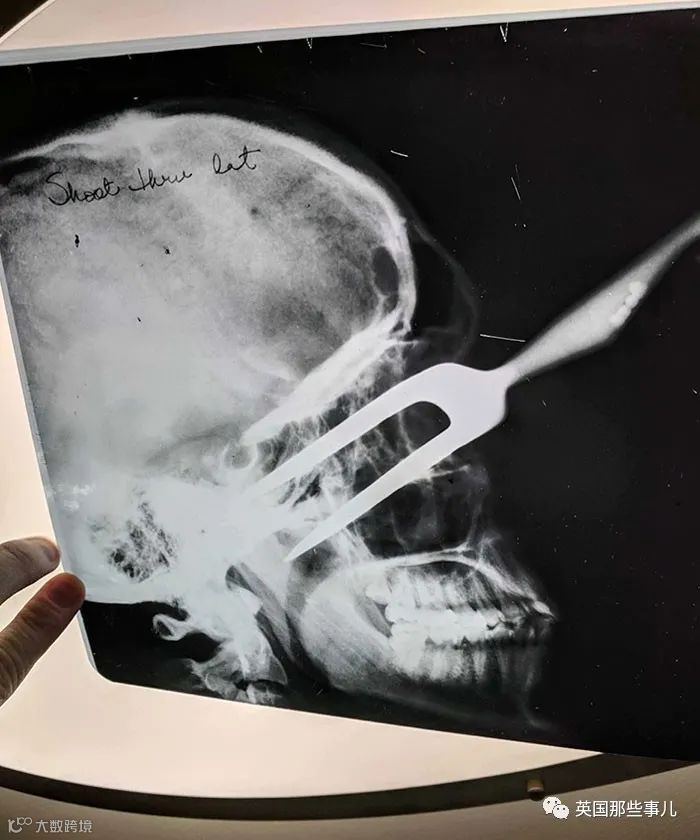

旧盒藏X光片

朋友家中发现旧盒子,内装多张X光片。